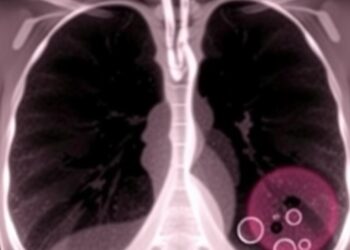

Engineered Immune Cells and Targeted Therapies Show Promise in Slowing Early Spread of Triple-Negative Breast Cancer, Study Finds

A groundbreaking preclinical study has introduced a promising paradigm in the fight against triple-negative breast cancer (TNBC), a notoriously aggressive ...